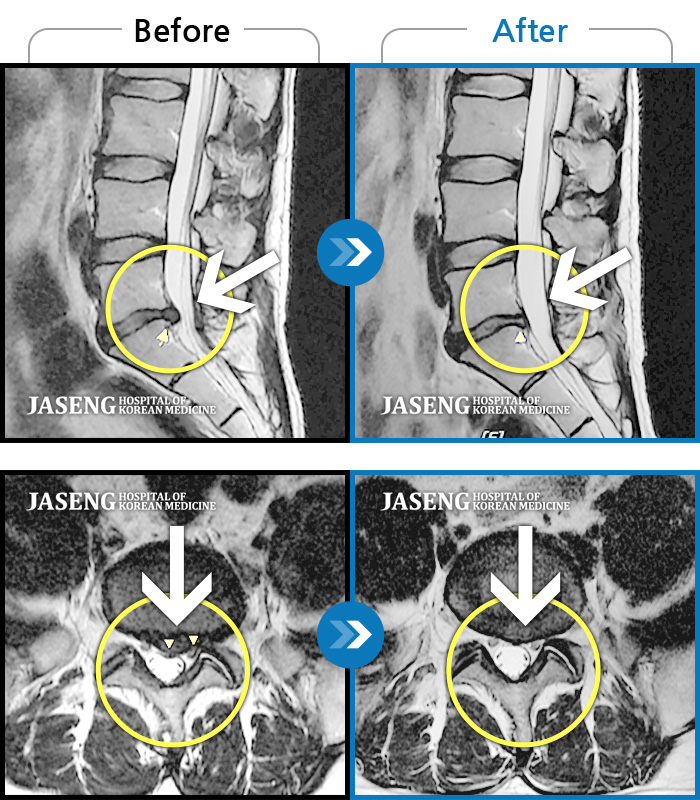

MRI 치료사례

허리디스크

해운대 · 강일환 원장

허리 골반 통증, 좌측 다리가 뒤로 당김

촬영시기

2015.03.28 ~ 2017.08.23

2017.12.26